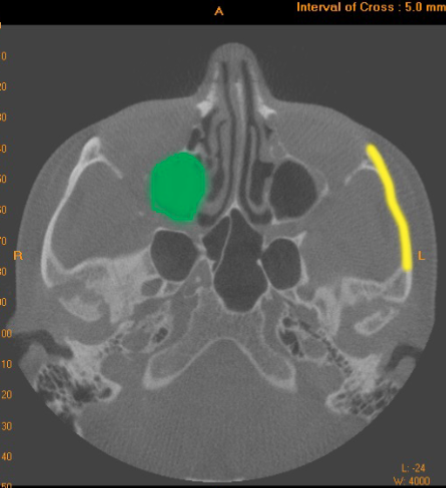

maxillary sinus

what is indicated by the GREEN dot

zygomatic arch

what is indicated by the YELLOW